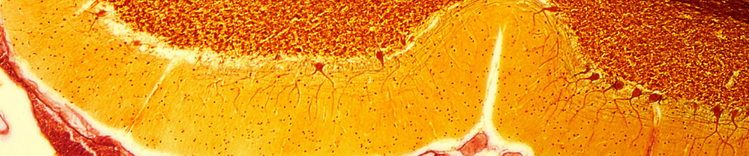

CELLULE DI PURKINJE NEL CERVELLO